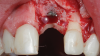

A patient presented for the restoration of an implant that had been placed at the site of tooth No. 9, which exhibited a residual soft-tissue deficiency and an undulating facial soft-tissue morphology (Figure 11). The objective of the treatment was to change the appearance and thickness of the facial soft tissue prior to crown placement to optimize the esthetics and prevent future soft-tissue dehiscence. After flap reflection (Figure 12), a graft was acquired from the patient's tuberosity to augment the supracrestal soft tissue (Figure 13). A volume-stable collagen matrix was then placed to further increase the thickness of the soft tissue adjacent to the implant body (Figure 14), and the flap was sutured closed (Figure 15). Following a 3-month healing period, a positive change in the soft tissue's morphology was apparent; however, its volume remained deficient when compared with that of tooth No. 8 (Figure 16). When the screw-retained crown was delivered, a second graft was acquired from the tuberosity and placed to further increase the volume of the supracrestal soft tissue (Figure 17 and Figure 18). A postoperative healing period of 4 months resulted in an ideal position of the margin of tooth No. 9 with regard to its contralateral counterpart as well as more natural looking soft-tissue morphology and excellent supracrestal soft-tissue thickness (Figure 19 and Figure 20). Eight months postoperatively, the position of the gingival margin and the thickness of the soft tissue had been maintained (Figure 21 and Figure 22).

(12.) Flap reflection to assess the position of the coronal aspect of the implant and facilitate soft-tissue grafting.

Figure 12

(13.) A soft-tissue graft from the tuberosity was placed to augment the supracrestal soft-tissue.

Figure 13